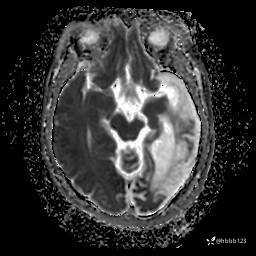

T2: